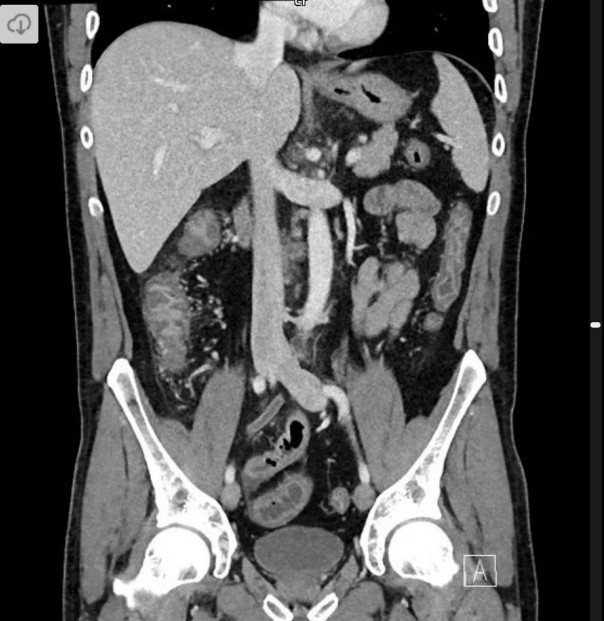

Abdominal pain

A 65-year-old man presents with central abdominal pain radiating to the back, associated with nausea and vomiting. He appears unwell. …